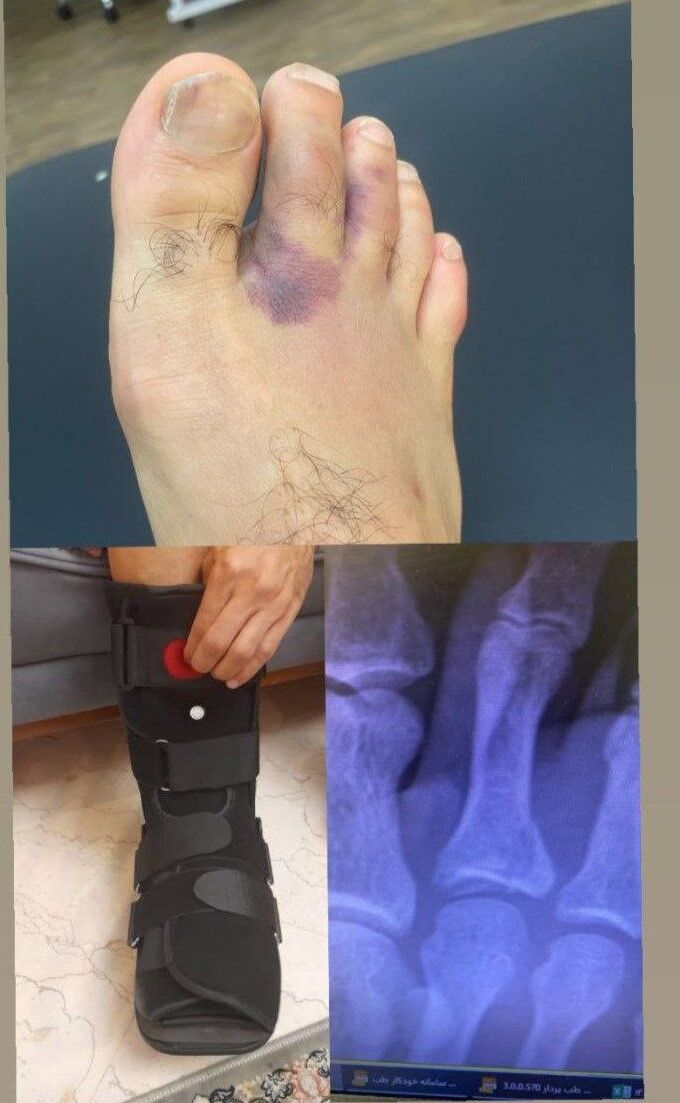

امروز عکسی از شکستگی پای عالیشاه منتشر شد که نشان می دهد انگشت پای این بازیکن شکسته و قادر به همراهی تیم پرسپولیس نخواهد بود.